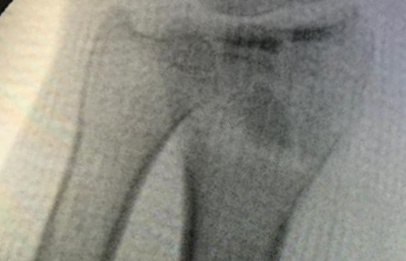

Cirugías de Codos - Cirugías de Muñecas y Manos

Los procedimientos más comunes en cirugía de la mano son aquellos destinados a reparar traumatismos, incluyendo lesiones de tendones, nervios, vasos sanguíneos, y articulaciones; huesos fracturados; y quemaduras, cortes, y otros daños de la piel.